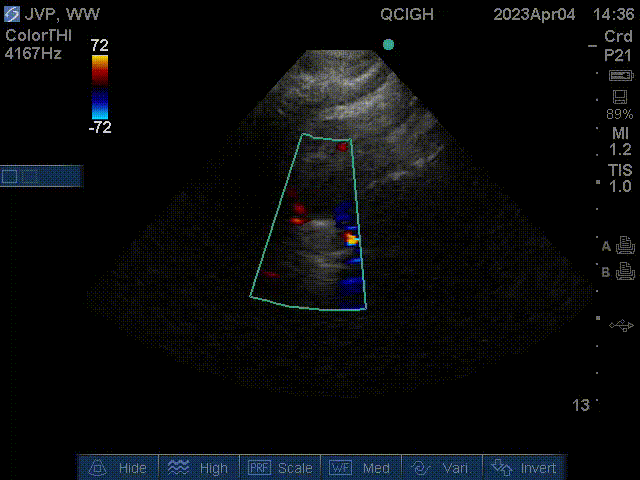

Aortic arch

This is a suprasternal color ultrasound of the aortic arch, and also showing flow in the left common carotid artery.